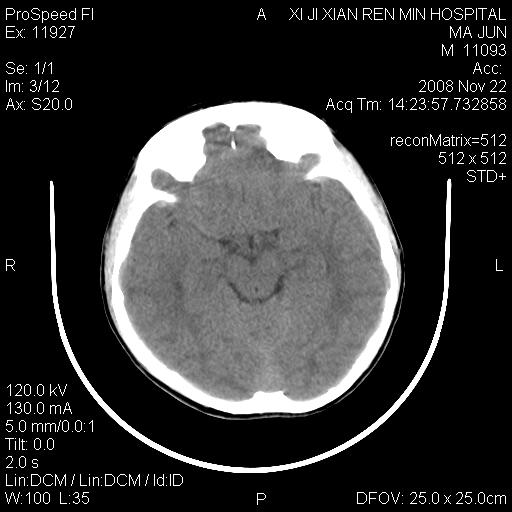

标题: PED1650:男 8岁 间断抽搐2年 两岁是在外院诊断脑瘫 当时CT示 [打印本页]

标题: PED1650:男 8岁 间断抽搐2年 两岁是在外院诊断脑瘫 当时CT示

双侧侧脑室前角,三角区旁及半卵圆中心区白质呈低密度改变,半卵圆中心区病灶呈片状融合趋势,无软化征像,脑室无扩张,各神经核团无异常改变,脑皮质无萎缩等征像,结合病史考虑髓鞘发育不良性脑白质病,异染性脑白质营养不良可能性大.不除外多发性硬化等其他改变,建议磁共振检查

脑白质减少,双侧侧脑室额角旁及半卵圆中心可见对称性略低密度影,边缘尚清,考虑脑白质发育不良